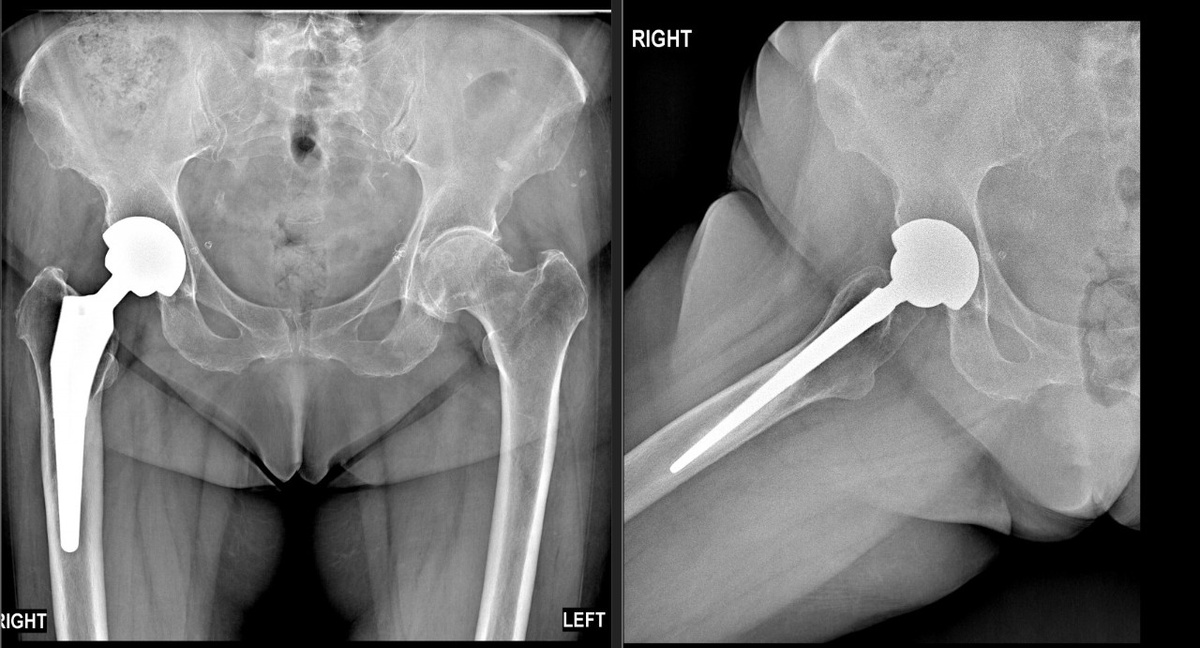

Случай 2: Импинджмент-синдром тазобедренного сустава (FAI)

У второго пациента при осмотре был положителен тест FADIR (боль при сгибании, приведении и внутренней ротации бедра). Рентген подтвердил диагноз: импинджмент-синдром. Из-за выраженных дегенеративных изменений в тазобедренном суставе - шейка бедра «соударяется» с краем вертлужной впадины, вызывая боль и мышечно-тонический синдром.